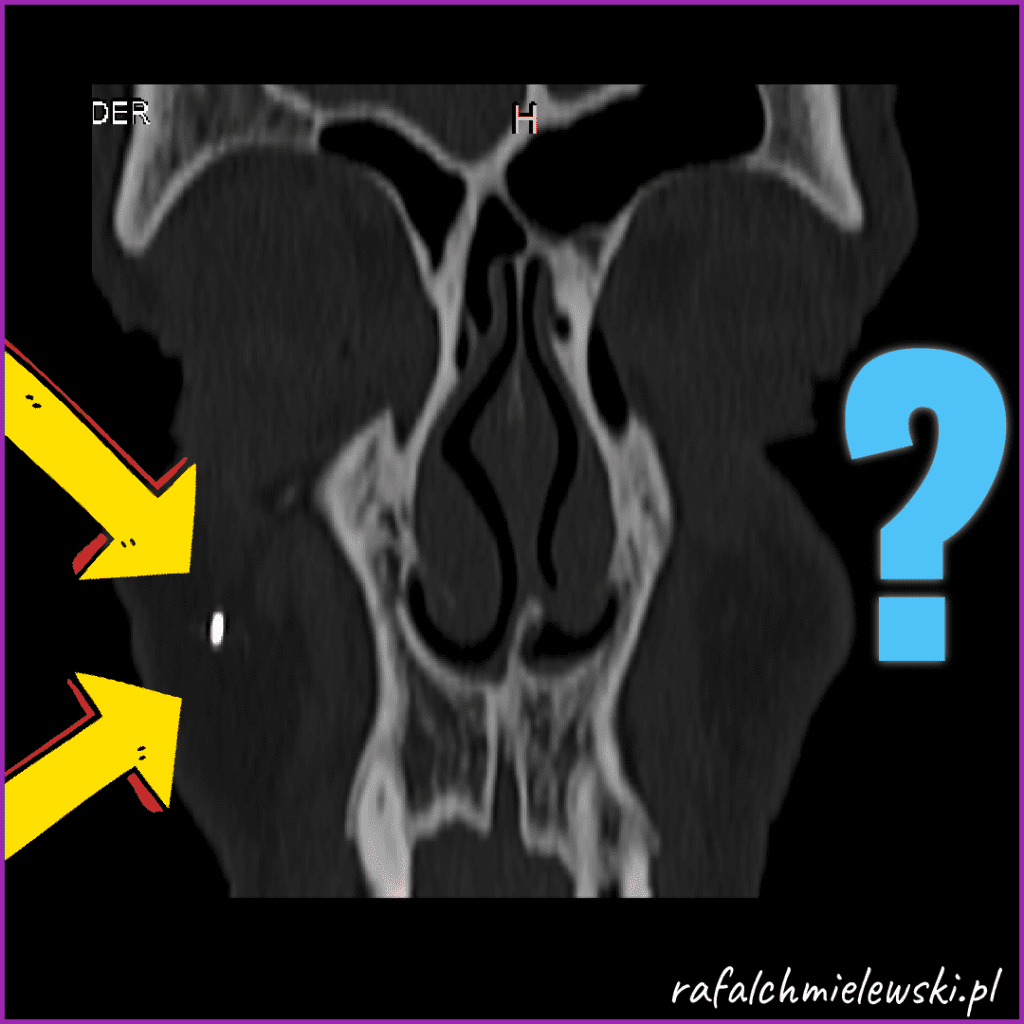

TK zatok - mataliczne ciało obce policzka

Metaliczne ciało obce, kształtu owalnego, zlokalizowane w tkankach miękkich policzka prawego. Reaguje przyciąganiem na zbliżenie magnesu. Przesuwalne pod jego wpływem, ale nie jest wyczuwalne palpacyjnie pod skórą.